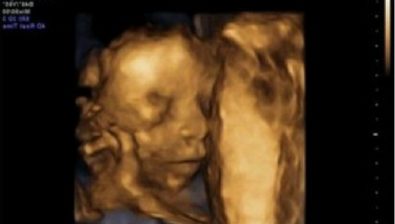

Ultrasound at 21 Weeks

Your baby’s organs are slowly maturing now, so his/her growth will be slower but steady. Swallowing amniotic fluid in your uterus, your baby is helping out the growth and development of the digestive system.

You might even be able to see your baby swallow on a live ultrasound screen.